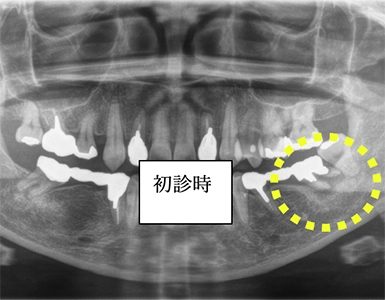

CASE1

歯周組織再生療法(保険診療)

術前

術後(1年後)

年齢・性別 50歳・女性

主訴 市の歯周病健診で歯周病を指摘された

診断名 広汎型慢性歯周炎ステージⅢグレードB

治療内容 歯周基本治療 歯石除去、ブラッシング指導により歯肉の炎症をできる限り改善し、その後歯周ポケットが深く歯槽骨の破壊が大きい部分に対して、歯周外科処置を行った。

治療期間 初診から歯周外科処置まで約5カ月、その後メインテナンス

費用 保険診療にて行う

リスク・副作用 術後の痛み、腫れ、出血が出ることがある

感染の可能性、腫れや再生不良が起こることがある

喫煙や清掃不良、炎症が重度の場合は組織再生の効果が十分得られないことがある

歯肉が引き締まる過程で知覚過敏が起こることがある。

CASE2

抜歯窩保存術 インプラント埋入術

初診時

左下7抜歯時

骨造成4か月後

インプラント手術後

年齢・性別 55歳・女性

主訴 左下の奥歯より嫌な匂いがする

診断名 左下第二大臼歯 歯根破折、慢性根尖性歯周炎

治療内容 左下7の歯根破折に起因する慢性根尖性歯周炎により抜歯が必要となった。患者様は機能性と審美性の回復を強く希望したため、抜歯後骨造成を行いインプラント治療を行った。

(GBR:歯根破折の炎症により、抜歯窩周囲の骨吸収が進んでおりこの状態ではインプラントを安定して埋入するだけの十分な骨量がないと判断し、GBR(骨造成)を行った。)

インプラント体と骨が強固に結合するまで通常3~6か月の治癒期間を設るため、インプラント体を埋入し、3か月経過後骨との結合を確認した後、型取りを行い仮歯で問題ないことを確認し、セラミックの人工歯(上部構造)を装着して治療完了した。

治療期間 インプラント埋入前に中断があったため1年7か月→初診からインプラント治療完了まで

費用 骨造成:110,000円

インプラント2本:902,000円(1本の場合は544,500円)